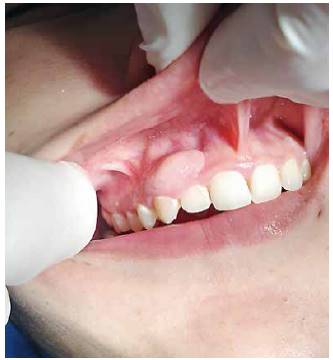

Al realizar el examen intraoral se observa un aumento de volumen de forma ovalada que va desde el margen gingival, abarcando encía adherida hasta muy cerca del fondo de vestíbulo. Esta lesión se extiende desde distal del diente 1.1 hasta mesial del 1.4. A la palpación, su consistencia es muy firme y tiene un color rosa pálido y presenta una base pediculada (Figura 1 y 2).

Se observa higiene oral deficiente y lesiones activas cervicales en dientes anteriosuperiores.